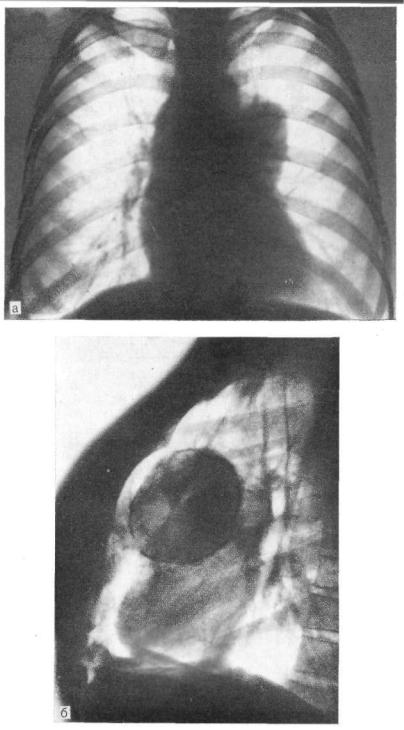

Рентгеновские снимки тератомы средостения: Диагностика и лечение

Раздел: Фотоэссе